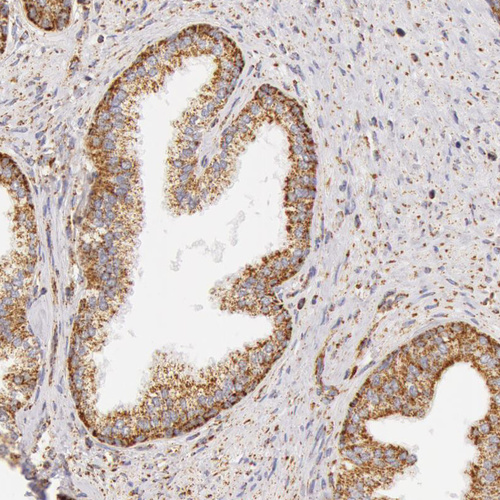

Immunohistochemical staining of human kidney, liver, prostate and small intestine using Anti-ATP5B antibody HPA001520 (A) shows similar protein distribution across tissues to independent antibody HPA001528 (B).